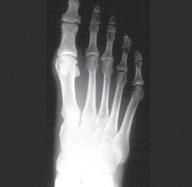

Hierna staat ook vast dat dr. Karolien Schwagten ons vervoegt over een kleine 1,5 jaar. Zij specialiseert zich in voet- en enkelchirurgie. Meer hierover in een van de volgende brieven.